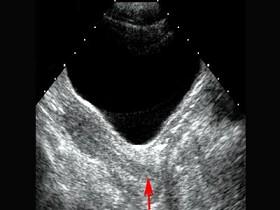

红色箭头所指部位是 ?(?)A.宫颈B.阴道C.子宫D.宫体E.以上都不是

问题 红色箭头所指部位是 ?(?)

选项 A.宫颈 B.阴道 C.子宫 D.宫体 E.以上都不是

答案 A